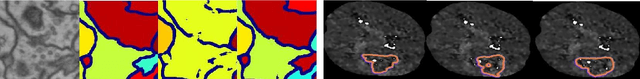

Abstract:Today, deep convolutional neural networks (CNNs) have demonstrated state-of-the-art performance for medical image segmentation, on various imaging modalities and tasks. Despite early success, segmentation networks may still generate anatomically aberrant segmentations, with holes or inaccuracies near the object boundaries. To enforce anatomical plausibility, recent research studies have focused on incorporating prior knowledge such as object shape or boundary, as constraints in the loss function. Prior integrated could be low-level referring to reformulated representations extracted from the ground-truth segmentations, or high-level representing external medical information such as the organ's shape or size. Over the past few years, prior-based losses exhibited a rising interest in the research field since they allow integration of expert knowledge while still being architecture-agnostic. However, given the diversity of prior-based losses on different medical imaging challenges and tasks, it has become hard to identify what loss works best for which dataset. In this paper, we establish a benchmark of recent prior-based losses for medical image segmentation. The main objective is to provide intuition onto which losses to choose given a particular task or dataset. To this end, four low-level and high-level prior-based losses are selected. The considered losses are validated on 8 different datasets from a variety of medical image segmentation challenges including the Decathlon, the ISLES and the WMH challenge. Results show that whereas low-level prior-based losses can guarantee an increase in performance over the Dice loss baseline regardless of the dataset characteristics, high-level prior-based losses can increase anatomical plausibility as per data characteristics.